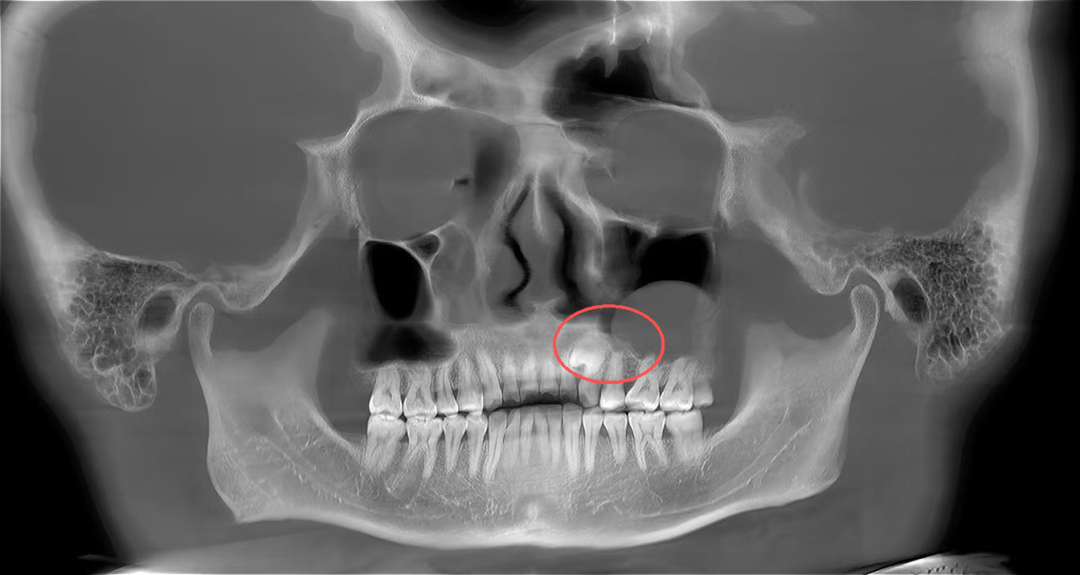

口腔颌面外科医生为其进行了详细的口腔检查并拍了放射片,结果显示:张先生的牙齿属于腭向埋伏阻生双尖牙,更值得注意的是,他的左侧上颌窦底还长有一个丘状软组织囊肿,且阻生牙的牙根与囊肿底部关系十分密切。

最终,专家团队决定采用“经拔牙创入路”的创新方案,一次手术解决两个问题。手术中,医生先精准拔掉埋伏牙,利用拔牙后形成的天然通道,将内镜伸进去直达囊肿位置,在清晰视野下把囊肿彻底清除,最后做好伤口缝合和保护。整个过程创伤小,还最大限度保护了上颌窦里的正常组织。

术后4个月,张先生复查时,伤口已经愈合得很好,没有任何不适,也没出现上颌窦炎等问题。拍片显示,上颌窦里的囊肿完全消失,拔牙的地方也长出了新骨头。